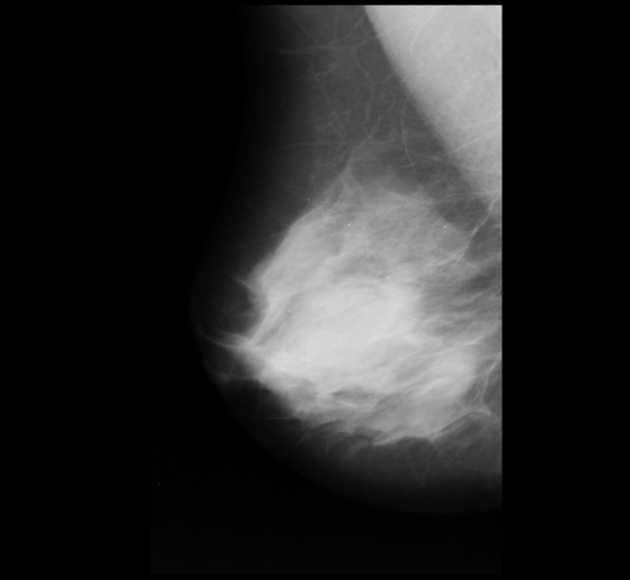

Neural networks require a large number of images as input for the training purposes. Because of limited resources of large dataset availability, the dataset used for this research is mini MIAS dataset [10]. It comprises of total 322 images which are further divided into a number of classes. Original size of each image in the dataset is 10241024. Sample images are shown in Figure 1.

3 Dataset